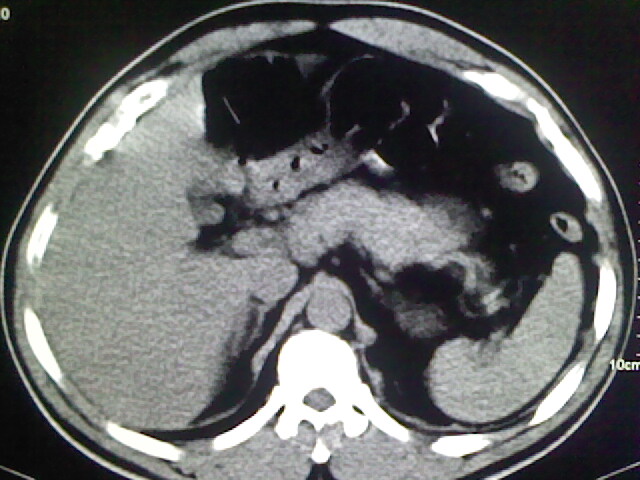

以下是引用zsl6918在2009-2-7 7:29:00的发言:[br]请提供介入的方式方法,肾及输尿管改变考虑与介入损伤有关,漏了,尿液外渗。

以下是引用余辉在2009-2-7 8:27:00的发言:[br]可能是硬化剂烧穿囊壁进入肾盂输尿管了,尿漏。不除外介入或碎石术后合并感染[br]患者术后怀疑结石,接着就碎石了?就怀疑没有确诊吗?碎石用的什么方法?气压弹道还是体外超声?如果这样的话责任人都难找

以下是引用随光逐影在2009-2-7 8:46:00的发言:[br]支持3楼意见。[br]另:不排除左肾及肾周感染可能。